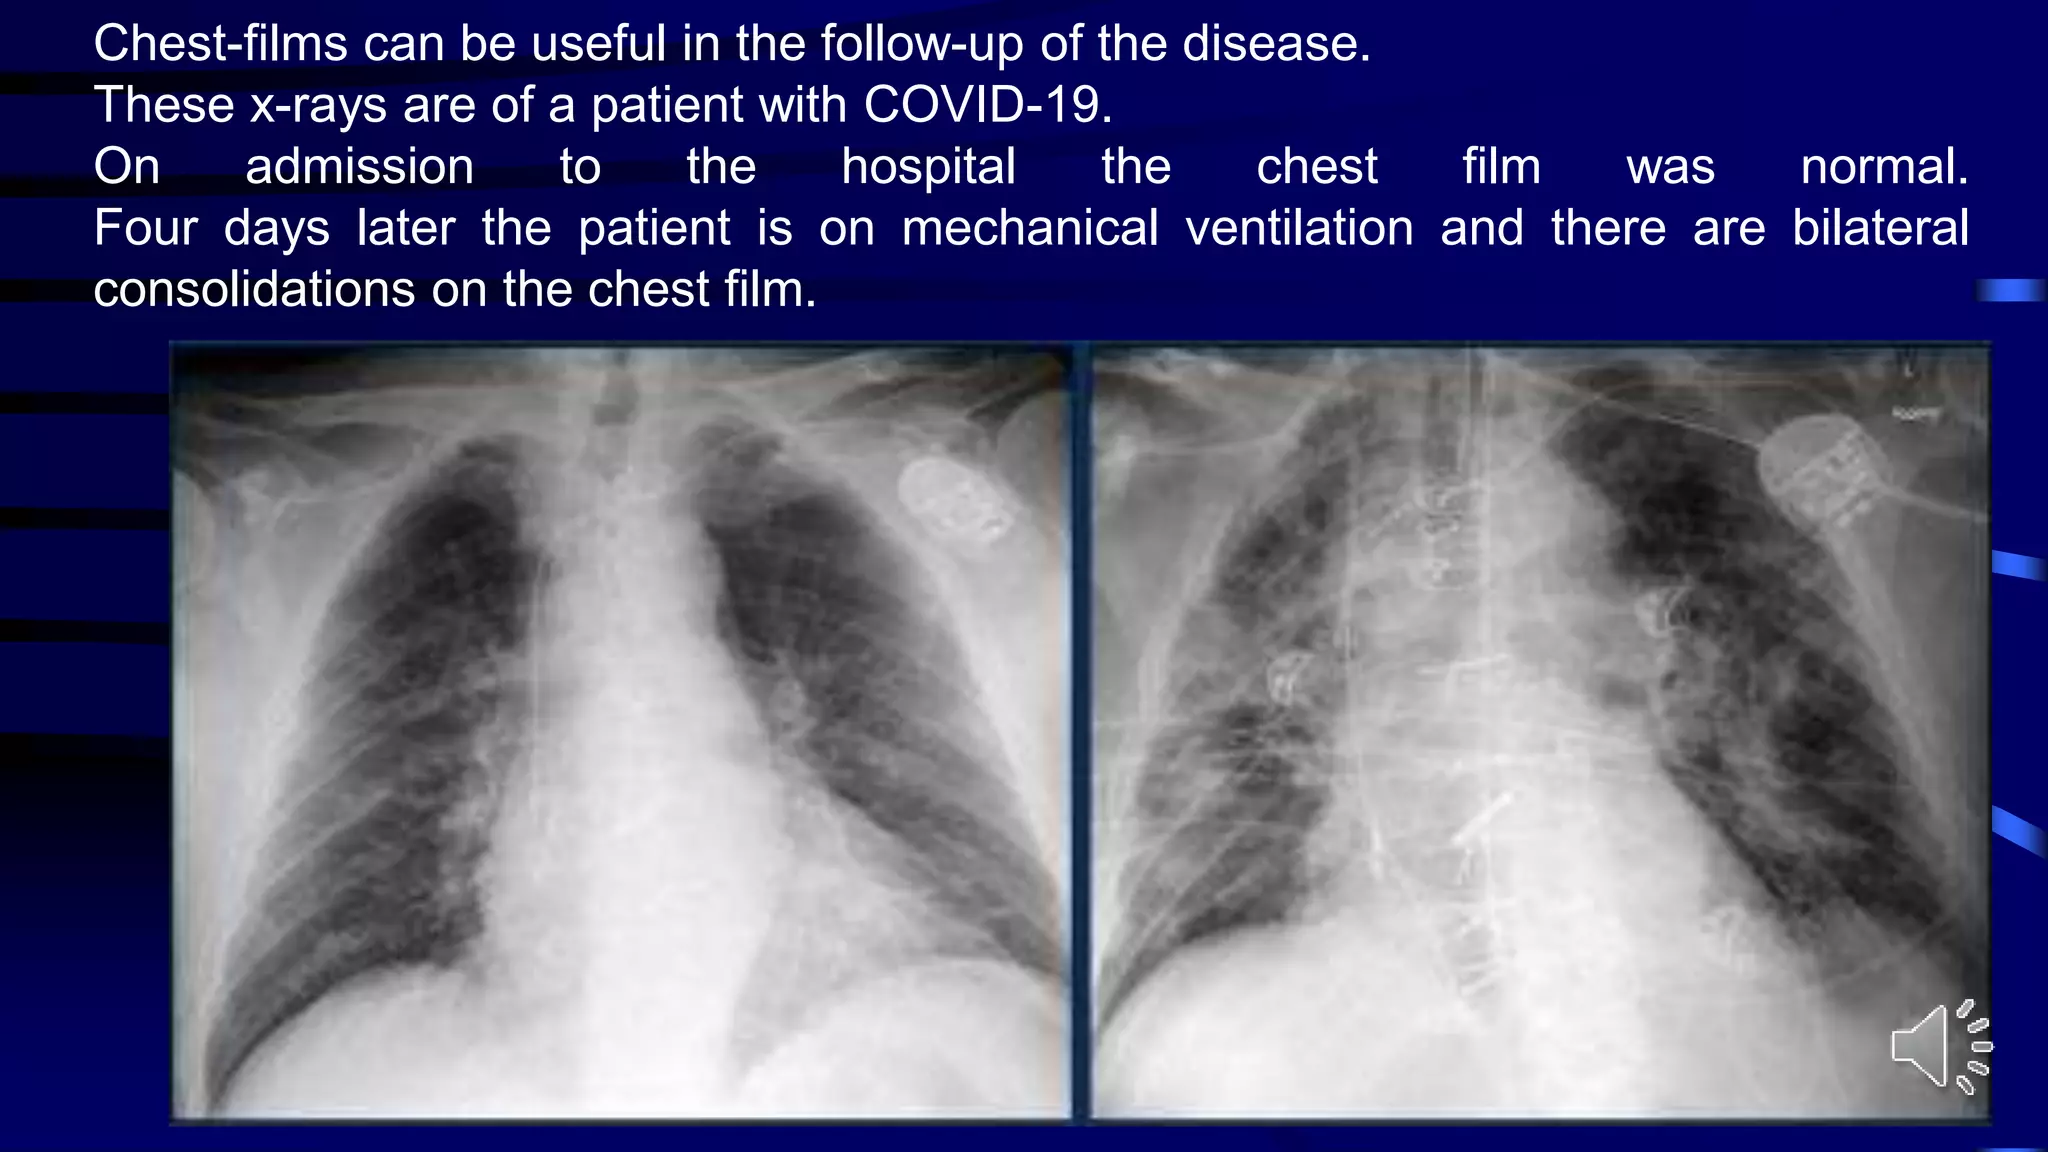

Chest-films can be useful in the follow-up of the disease.

These x-rays are of a patient with COVID-19.

On admission to the hospital the chest film was normal.

Four days later the patient is on mechanical ventilation and there are bilateral

consolidations on the chest film.